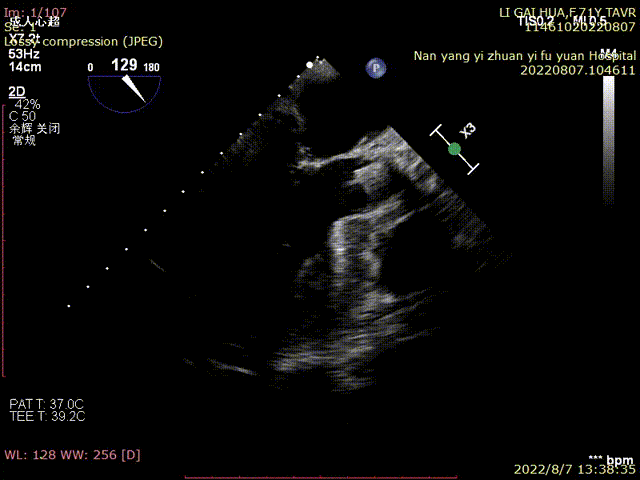

术前TEE超声:

超声明确瓣膜位置

超声评估

瓣膜释放后超声评估:

术中,心外体外循环科郑军医师全程待命。彩超室张俊鹏老师全程跟台,术后行超声探查未见瓣周漏,血压改善。